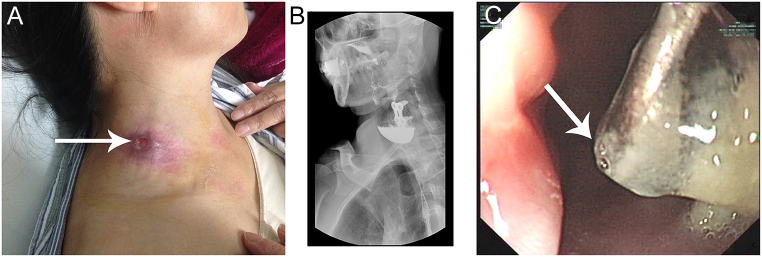

Esophageal perforation is a rare but serious complication that can occur post-cervical spine surgery. This case report presents the clinical course, diagnostic challenges and management strategies of a patient who had a late-diagnosis esophageal perforation after anterior cervical spine surgery (ACSS). A woman in her 50s underwent ACSS for cervical spondylosis. Three months postoperatively, she experienced persistent right neck and shoulder pain. Despite multiple consultations, an esophageal perforation was only diagnosed 10 years later when a neck mass ruptured, discharging food debris. Surgical management included removing the anterior cervical plate and reconstruction with a sternocleidomastoid muscle flap. Postoperatively, she faced wound complications, and the perforation failed to heal despite multiple debridement and stent placements. Ultimately, complete excision of the diverticulum, repair of the perforation and muscle flap reconstruction led to her recovery, with no recurrence over an 8-year follow-up. We reviewed the literature on cases with esophageal perforation occurring more than 10 years after anterior cervical surgery and summarized the treatment experiences. This case underscores the diagnostic challenges and delayed presentation of esophageal perforation post-ACSS. Early recognition and multidisciplinary management are essential. In cases of late perforation, hardware removal, diverticulum excision and a muscle flap are critical to achieving successful closure of the esophageal lesion, preventing recurrence and ensuring comprehensive repair. Addressing esophageal diverticula during perforation treatment is crucial to prevent recurrence and ensure thorough repair. This highlights the need for high clinical suspicion and a coordinated surgical approach to improve patient outcomes.